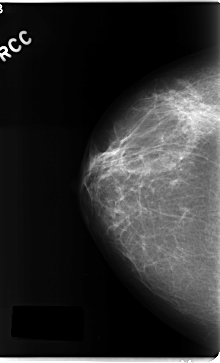

C_0161_1.RIGHT_CC

RIGHT_CC LINES 4712 PIXELS_PER_LINE 2848 BITS_PER_PIXEL 12 RESOLUTION 50 NON_OVERLAY